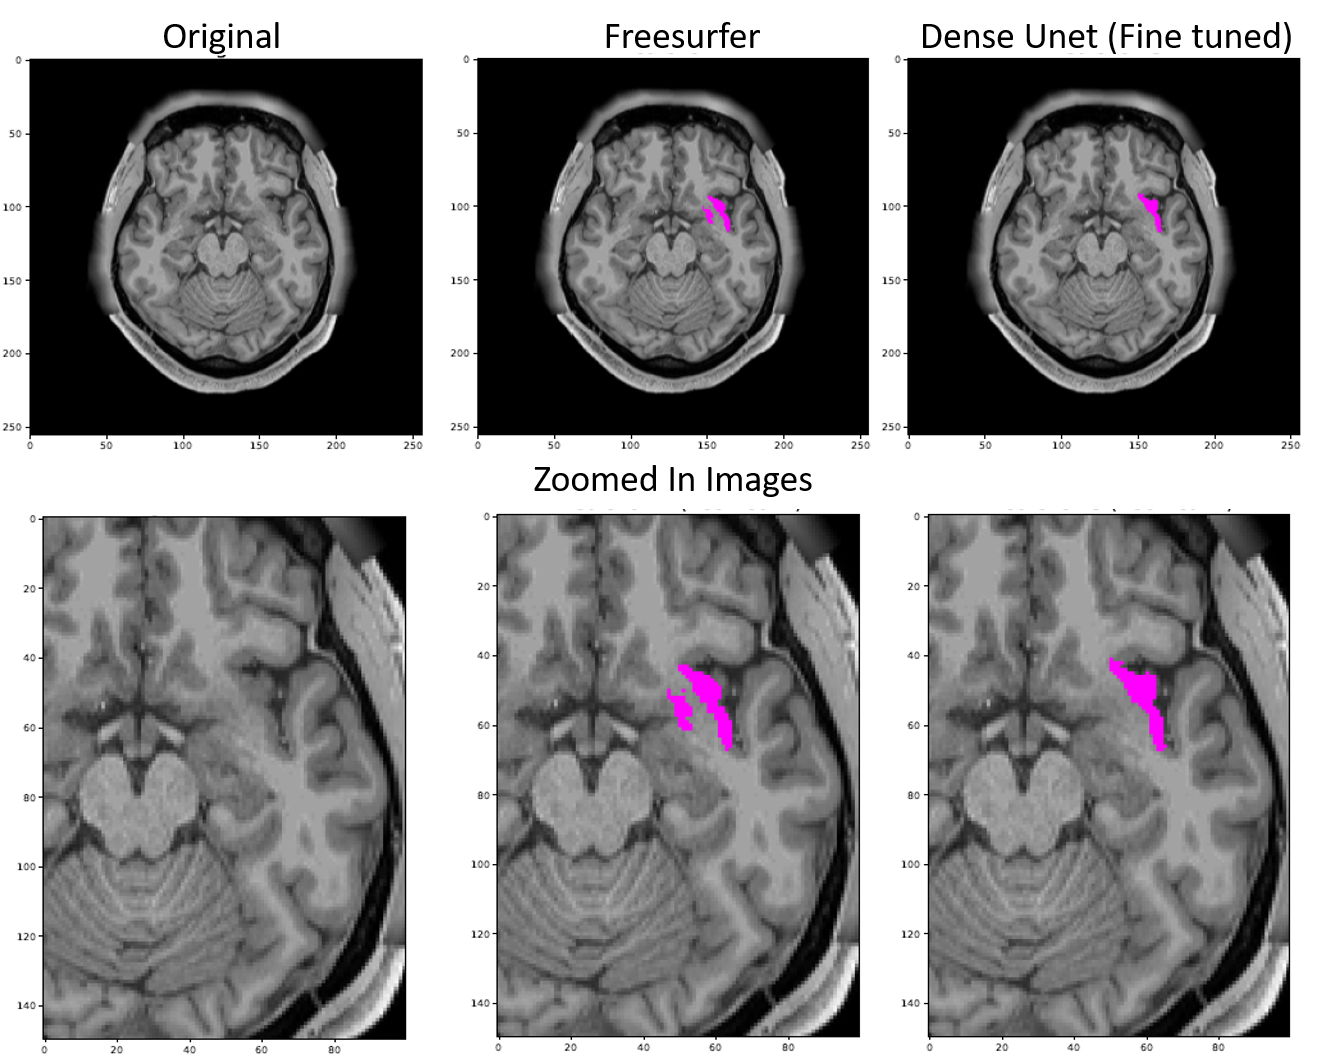

Pallidum

Figure 17 shows the difference in the segmentation outputs of Freesurfer and the proposed model.

Refer to caption

Figure 17: The image shows the original slice of an MRI, Freesurfer’s (FS’s) prediction for Pallidum and the proposed model’s prediction of the same. It is evident that FS’s prediction don’t obey the boundaries and are non-natural looking grainy segmentation whereas the proposed model’s prediction obey the segment boundaries and are much more natural looking